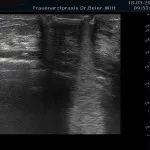

Mammasonographie:

Ultraschall_12